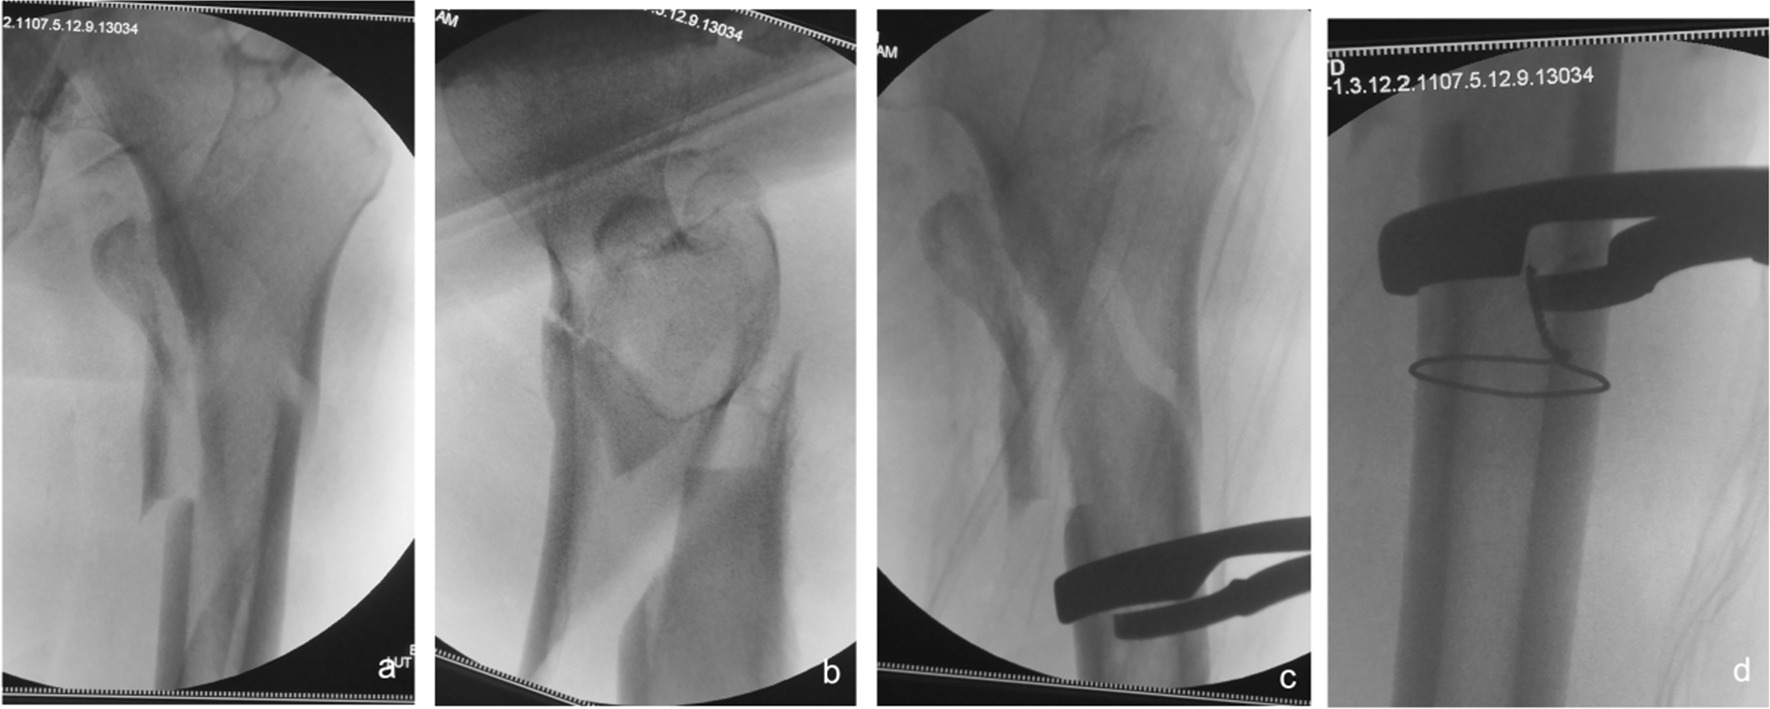

Fig. 5.

Anteroposterior and lateral X-ray films before and after reduction in patients with difficulty in reduction on the coronal plane and internal rotation displacement of the proximal fracture segment a, b Before reduction; c, d After reduction (one head placed on the inner side of the proximal fracture segment and the other head on the outer side of the greater trochanter)